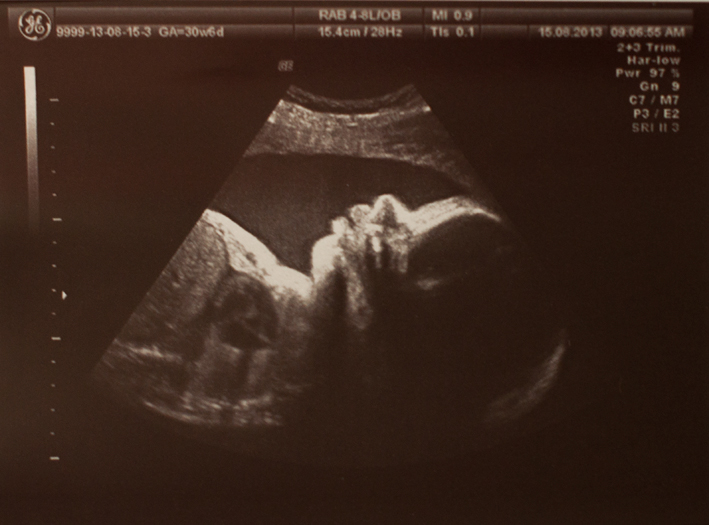

УЗИ, КТГ, доплерБрешу, 32 стартует завтра. Сегодня поворочали козявку на плановом УЗИ. Вся она такая средненькая, идем по сроку, весим 1, 6380. Мне и это сложно представить, где у меня там размещается цельный человеческий индивид с окружностью головы 28 см. Чудо какой компактный ребенок. Лежит опять головой вниз - перевернуться раз в неделю - это самое оно, молодец хоть от пуповины уворачивается, без обвития. Плаценту я уговорила, она поднялась на нужную высоту, долой мысли о кесаревом!

Физией мы определенно в папаху - носяра на пол лица и губы-вареники (естественный ботокс). Амниотическая жидкость, плацента в норме - есть куда плавать, есть обо что долбиться. Печалька: диск нам не записали, только фото, потому, что шла я по направлению, а отдельно за видео заплатить при таком порядке нельзя...